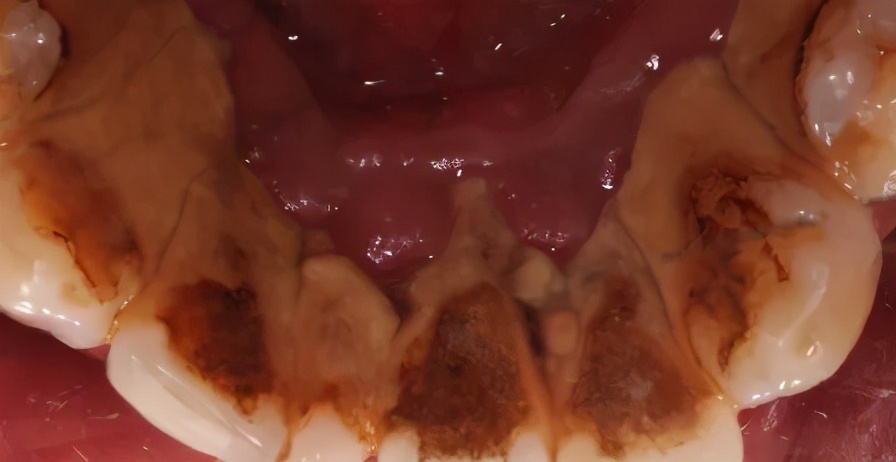

你见过这么厚的牙结石吗?

下图牙表面黄色的,就是 牙结石